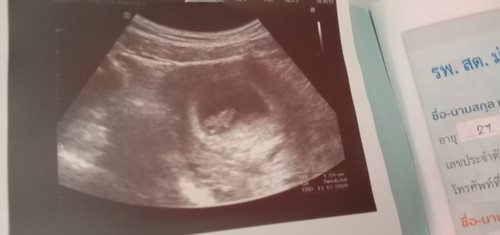

อัตตราเซาว์ครั้งแรกหมอบอกว่า7w6dตัวน้อง1.05ซมเห็นครั้งแรงมีความสุขมากน้องเเข็งแรงดี